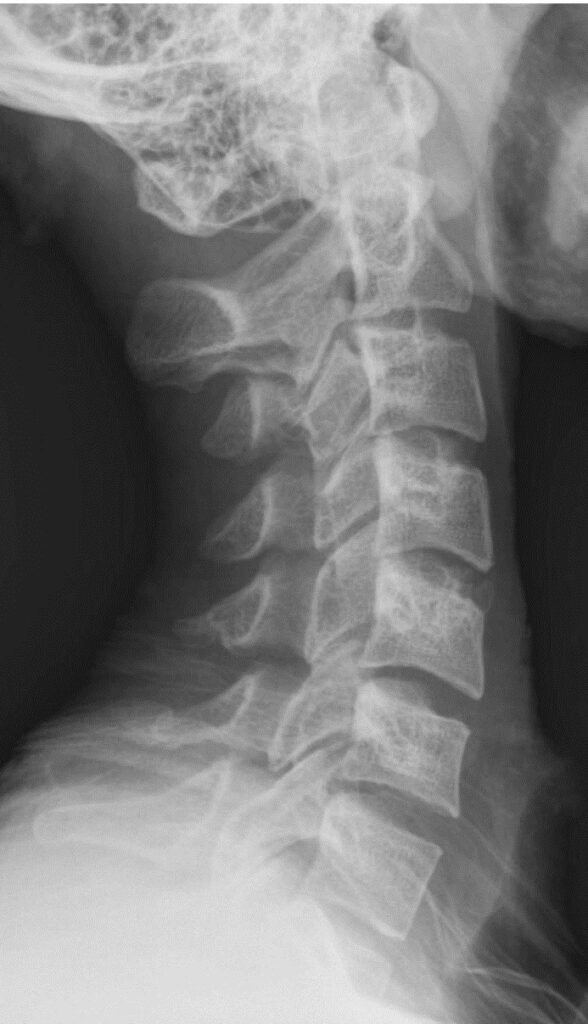

Ideally, your neck should have a slight curve. This is called cervical lordosis.

If this curve becomes straight, the head flexes double. This change creates a double chin.